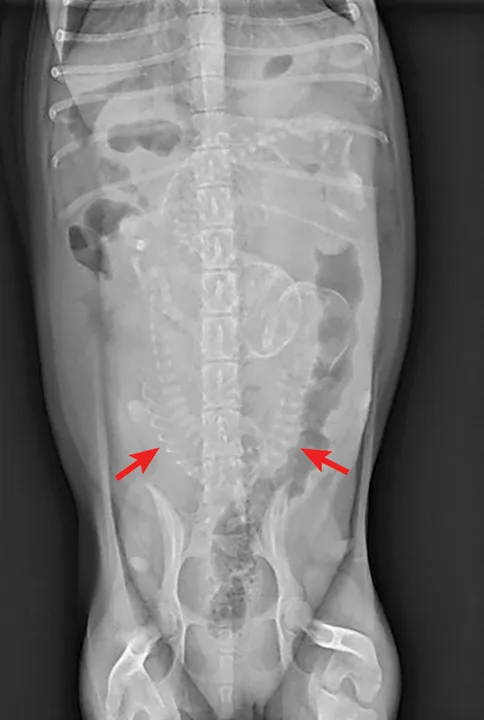

Radiographic evidence of malpositioned fetuses, malformed fetuses, or a large fetus exceeding the maternal pelvic canal diameter

Ventrodorsal abdominal radiograph of a pregnant bitch presenting for dystocia. Note the malpositioned fetus oriented transversely to the pelvic canal. Radiographs courtesy of Amanda A. Cavanagh, DVM, DACVECC

If the bitch is examined after day 44 of gestation, when fetal skeletons mineralize, radiographs should be obtained to determine litter size, fetal positioning, and signs of fetal death.2,8 (See Figure 1 & Figure 2.) Ultrasonography is the ideal imaging modality for determining fetal stress and viability.2